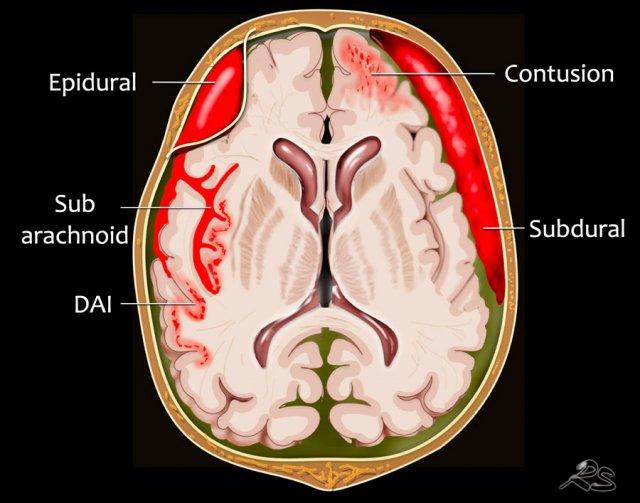

Vị trí của xuất huyết

Xuất huyết ngoài trục – Xuất huyết nội sọ ngoài não

- Xuất huyết dưới nhện là chảy máu cấp tính dưới màng nhện. Thường gặp nhất trong trường hợp vỡ phình động mạch hoặc do chấn thương.

- Tụ máu dưới màng cứng là chảy máu giữa lớp trong của màng cứng và màng nhện của màng não. Thường xảy ra do rách chấn thương các tĩnh mạch cầu nối đi qua khoang dưới màng cứng ở những bệnh nhân đang dùng thuốc chống đông máu.

- Tụ máu ngoài màng cứng là chảy máu trong khoang ảo giữa màng cứng và hộp sọ. Gặp trong trường hợp gãy xương thái dương kèm vỡ động mạch màng não giữa.

Xuất huyết trong trục – xuất huyết trong não

- Dập não xuất huyết là các ổ xuất huyết nhỏ sau chấn thương nằm gần hộp sọ tại vùng chấn thương trực tiếp và đối diện, thường gặp nhất ở nền thùy trán và phần trước thùy thái dương. Đôi khi kết hợp với tụ máu dưới màng cứng hoặc xuất huyết dưới nhện.

- Tổn thương sợi trục lan tỏa (DAI). Tổn thương lan tỏa tại vùng ranh giới chất xám – chất trắng, gặp trong các chấn thương tốc độ cao. CT có độ nhạy thấp. Quan sát rõ hơn trên MRI.